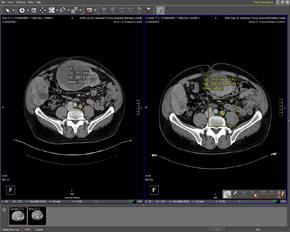

Lymph nodes are a primary site of metastatic spread for almost all malignant tumors. Tracking changes to lymph node ...

Definiens is debuting its newly launched Version 2 of Definiens LymphExpert, a CAD software application designed to ...